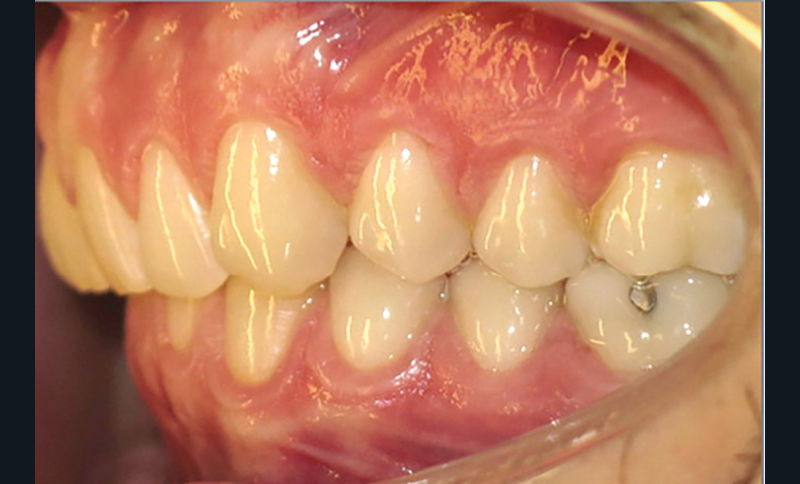

Examen endobuccal (fig. 2a-e)

L’arcade maxillaire est asymétrique, en hémi-lyre droite. Elle présente une mésio-position du secteur 1 en lien avec un encombrement antérieur estimé à 4 mm, se traduisant par une palato-position de la 12 et une rotation de la 11. On observe également des mésio-rotations des premières molaires et une palato-version incisive. L’arcade mandibulaire est ellipsoïde et présente un léger encombrement incisif (1 mm).

Concernant les relations occlusales, on observe une classe II complète subdivision droite. Le surplomb est absent et le recouvrement augmenté, estimé à 4 mm, a provoqué une usure des bords libres de 11 et 21 par attrition. Dans la dimension transversale, on constate une endoalvéolie maxillaire, ainsi qu’une concordance des médianes incisives entre elles, mais toutes deux déviées à droite par rapport au plan sagittal médian.